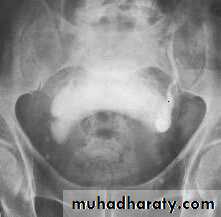

INVESTIGATIONS

Routine

• G.U.E• KFT.

• PSA.

• IPSS.

Optional

• U/S.

• IVU.

• UDS.

• CYSTOSCOPY.